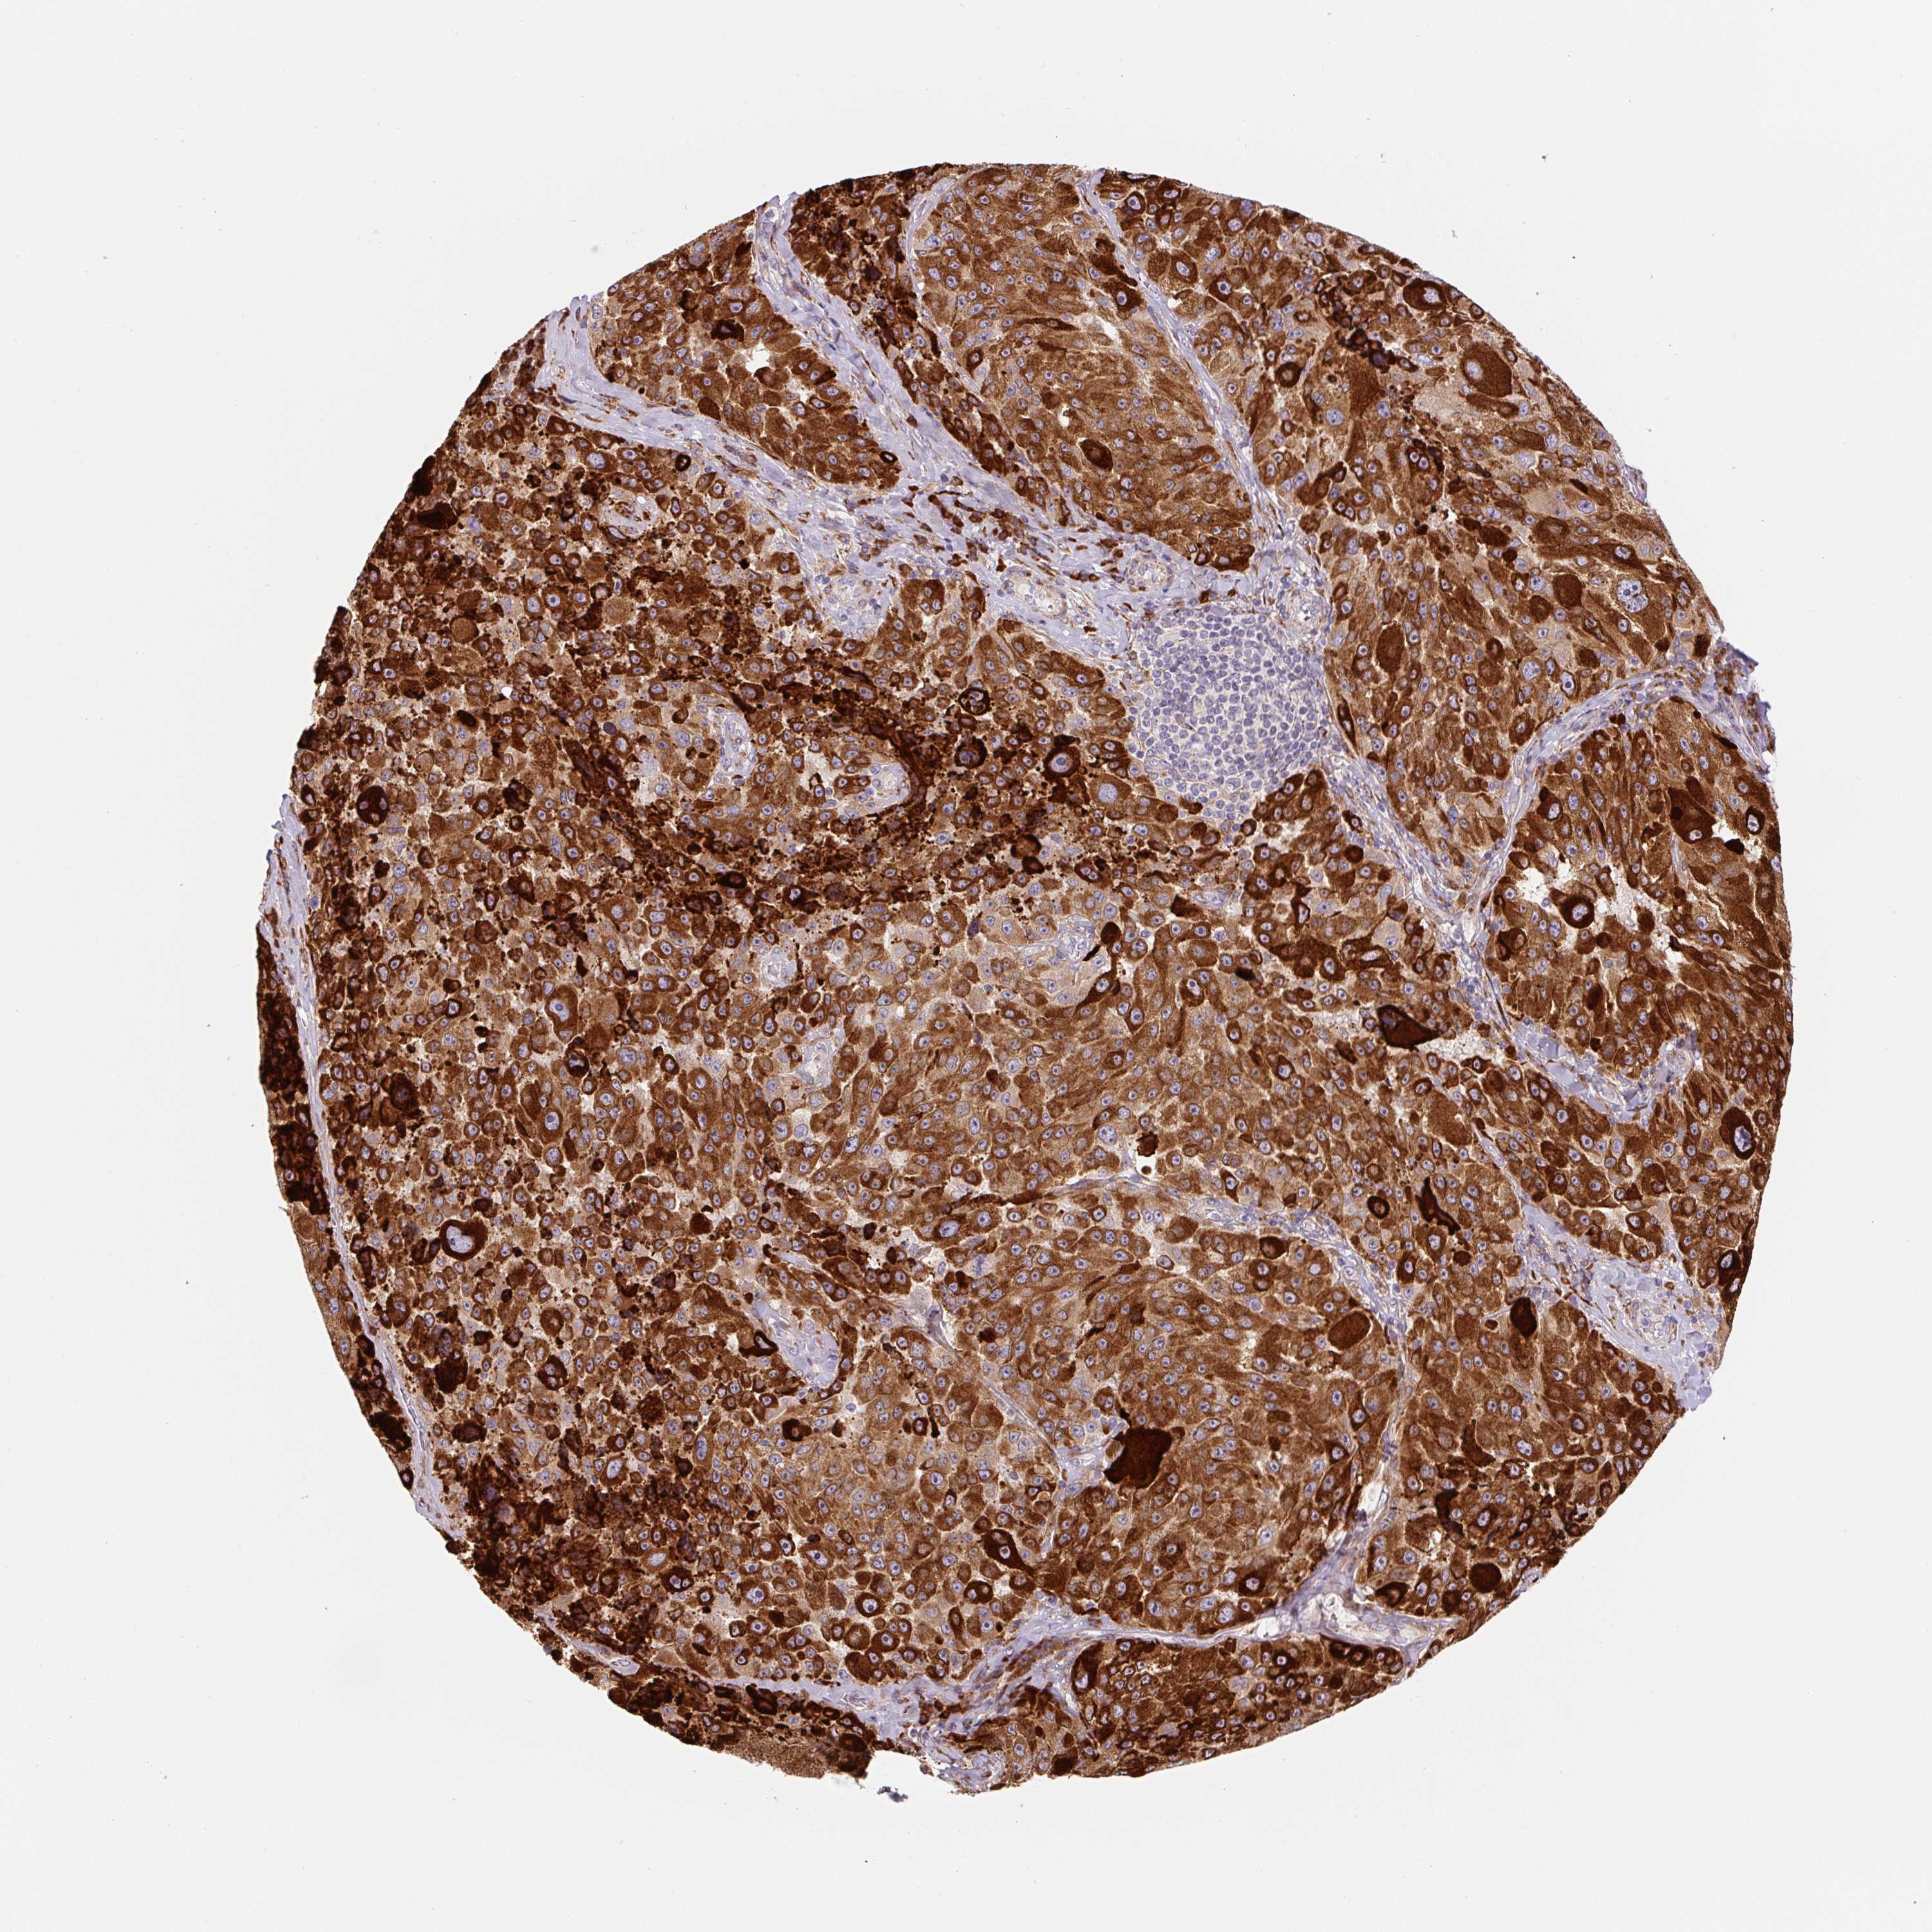

MELANOMA - Protein expressioni

A mouse-over function shows sample information and annotation data. Click on an image to view it in a full screen mode. Samples can be filtered based on level of antibody staining by selecting one or several of the following categories: high, medium, low and not detected. The assay and annotation is described here.

Note that samples used for immunohistochemistry by the Human Protein Atlas do not correspond to samples in the TCGA dataset.

Antibody stainingi

Antibody staining in the annotated cell types in the current human tissue is reported as not detected, low, medium, or high, based on conventional immunohistochemistry profiling in selected tissues. This score is based on the combination of the staining intensity and fraction of stained cells.

Each image is clickable and will lead to virtual microscopy that enables deeper exploration of all samples and also displays staining intensity scores, fraction scores and subcellular localization as well as patient and tissue information for each sample.

Antibody HPA054579

Staining

High

Medium

Low

Not detected

Intensity

Strong

Moderate

Weak

Negative

Quantity

>75%

75%-25%

<25%

None

Location

Nuclear

Cytoplasmic/membranous

Cytoplasmic/membranous,nuclear

Malignant melanoma, NOS

Malignant melanoma, Metastatic site